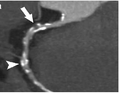

CT-Angiographie; mittels multiplanarer Reformation (hier die sog. curved MPR) sind auch Schnittdarstellungen entlang beliebiger Gefäßverläufe möglich, wodurch die gezeigte Arteriosklerose sehr gut visualisiert werden kann.